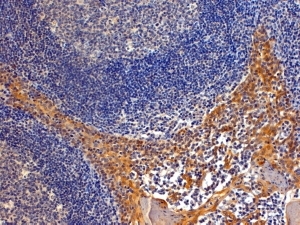

- Main image

- Experimental details

- Immunohistochemistry: paraffin embedded Human Tonsil. (Steamed antigen retrieval with Tris/EDTA buffer pH 9) stained with ARG63366 anti-RANBP8 / IPO8 antibody at 4 µg/ml dilution followed by HRP-staining. Similar results were obtained after antigen retrieval at pH9.